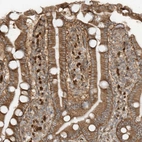

Immunohistochemical staining of human duodenum shows moderate cytoplasmic positivity in glandular cells.